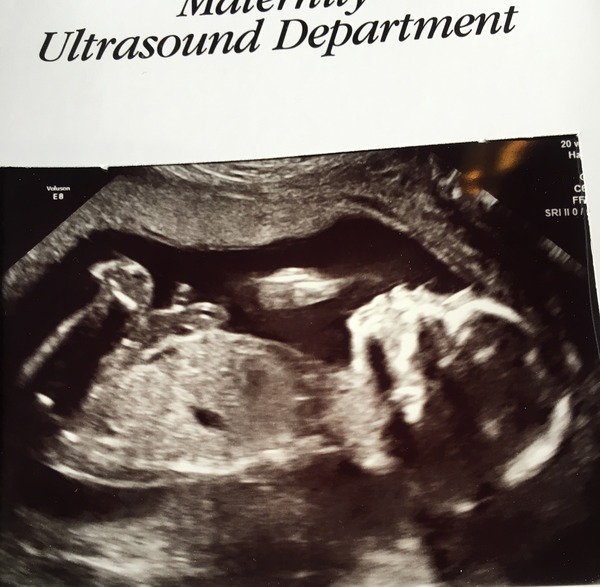

I had my 20week scan this morning. Everything is absolutely fine! Such a relief and isn't it amazing to see your baby wriggling around and looking like a real baby. We decided not to find out the sex although I must admit to trying to peer between its legs at every opportunity. Had no idea what I was looking for though so still Team Yellow!

Also- my restraint is not that excellent. I've just been scouring all the scan pics to see if there's any hint of the sex. No joy! Although pic attached if anyone wants to have a go...